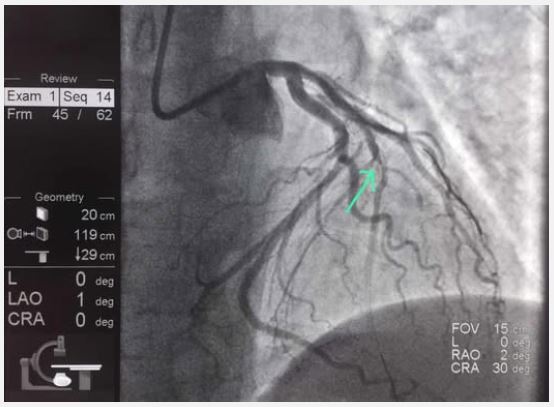

Nine days later, after consuming marijuana again, the patient presented with unstable angina. Clinical evaluation revealed normal bilateral vesicular breath sounds, a soft, painless abdomen, and no edema. Troponin level was 0.15 ng/ml (normal <0.06), ECG revealed ST-segment elevations in V2-V6 (Figure 2), and echocardiography showed apical akinesia, indicative of transmural MI. Coronary angiography revealed neoatherosclerosis with an unstable plaque and mural thrombus in the mid-segment of Left Anterior Descending (LAD) artery (Figure 3). Primary PCI was performed.